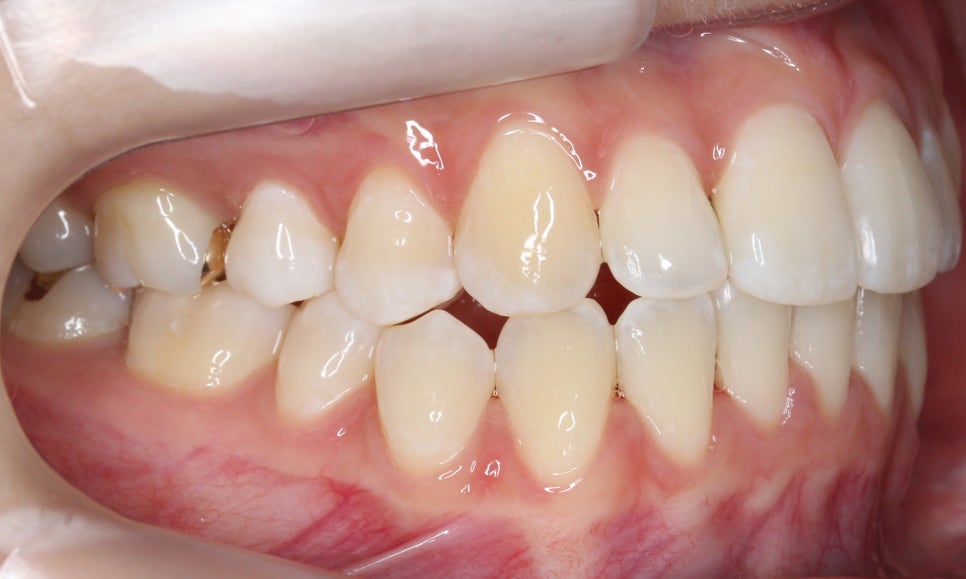

신논현치과 자가결찰브라켓 Case의

교정 전 치아 상태입니다.

정면에서 본 치아의 전체적인 모습을 보면

상대적으로 구치부보다 전치부의 치열이

삐뚤어져 있는 상태로 12번(측절치)의

반대교합이 눈에 띄는 모습입니다.

치아 개방 시 상악과 하악의 정중선을 보면

대각선으로 삐뚤어져 있는 것을 확인할 수 있는데요,

안모의 중심이 틀어져 있기 때문에 치아 개방-교합 시

한쪽으로 힘이 가중될 가능성이 있습니다.

overbite 사진을 보면 상악 좌측 측절치가

하악보다 뒤쪽으로 교합되는 모습을

확인할 수 있는데요, 이렇듯 일부 치아에

반대교합 증상이 나타날 경우 2D교정이나

투명교정을 통해 단기간에 심미적인

치아 교정이 가능합니다.

전치부의 돌출 정도를 확인할 수 있는

overjet 수치는 비교적 돌출감이 없는 모습으로

거꾸로 물리는 측절치를 해결한다면

스마일라인의 심미성을 보완할 수 있을 것으로 보입니다.

좌우의 교합평면을 보면 구치부의 교합은

크게 틀어진 부분 없이 양호한 상태인데요,

상악의 경우 송곳니의 위치나 각도도

좋기 때문에 부분교정도 가능하나

전체적인 교합을 바르게 하기 위해

자가결찰브라켓인 클리피씨교정 장치를

적용하여 전체교정을 진행하였습니다.

상악의 경우 설측으로 뻐드러져 있는

측절치의 바른 교정이 중요한 포인트이기 때문에

이를 중심으로 교정 계획을 수립하였습니다.

또한 미세하게 발견되고 있는 crowding으로 인해

삐뚤어진 정중선 역시 바른 각도로 교정하도록 하였습니다.

하악은 상악에 비해 심하게 틀어지진 않았지만

전치부의 치아들이 회전된 모습이 나타나기 때문에

이를 바르게 교정하여 전치부의 심미성을

보완하도록 하였습니다.